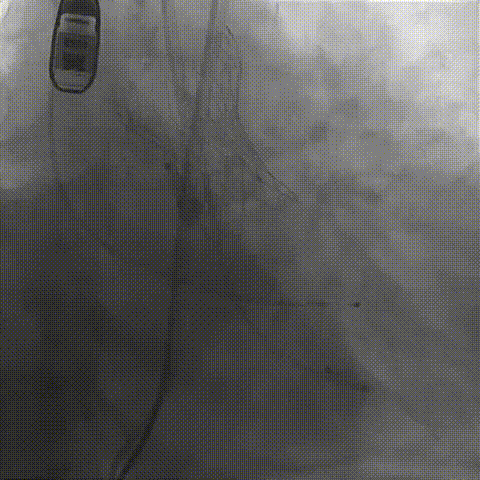

瓣膜(AV29)工作位正交体位造影位置良好,左冠显影正常

瓣膜(AV29)完全脱钩释放后23mm球囊充分后扩,冠脉灌注良好

最后造影

术后血流动力学

瓣膜工作状态良好,极微量瓣周漏,血流动力学有效改善